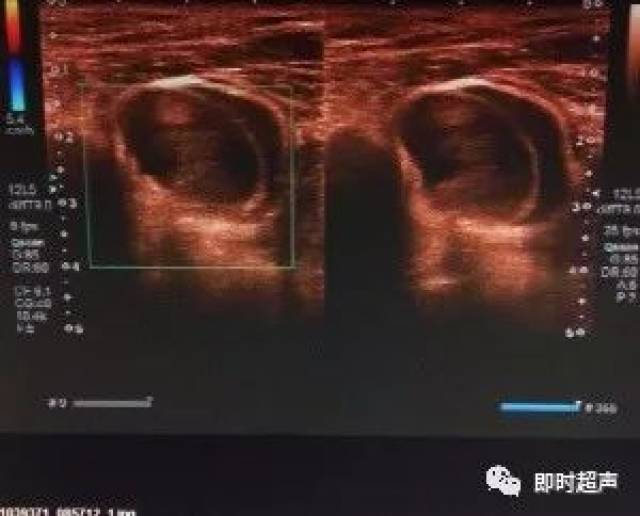

【病例】腹部疝超声诊断

经典病例-----腹壁疝请欣赏